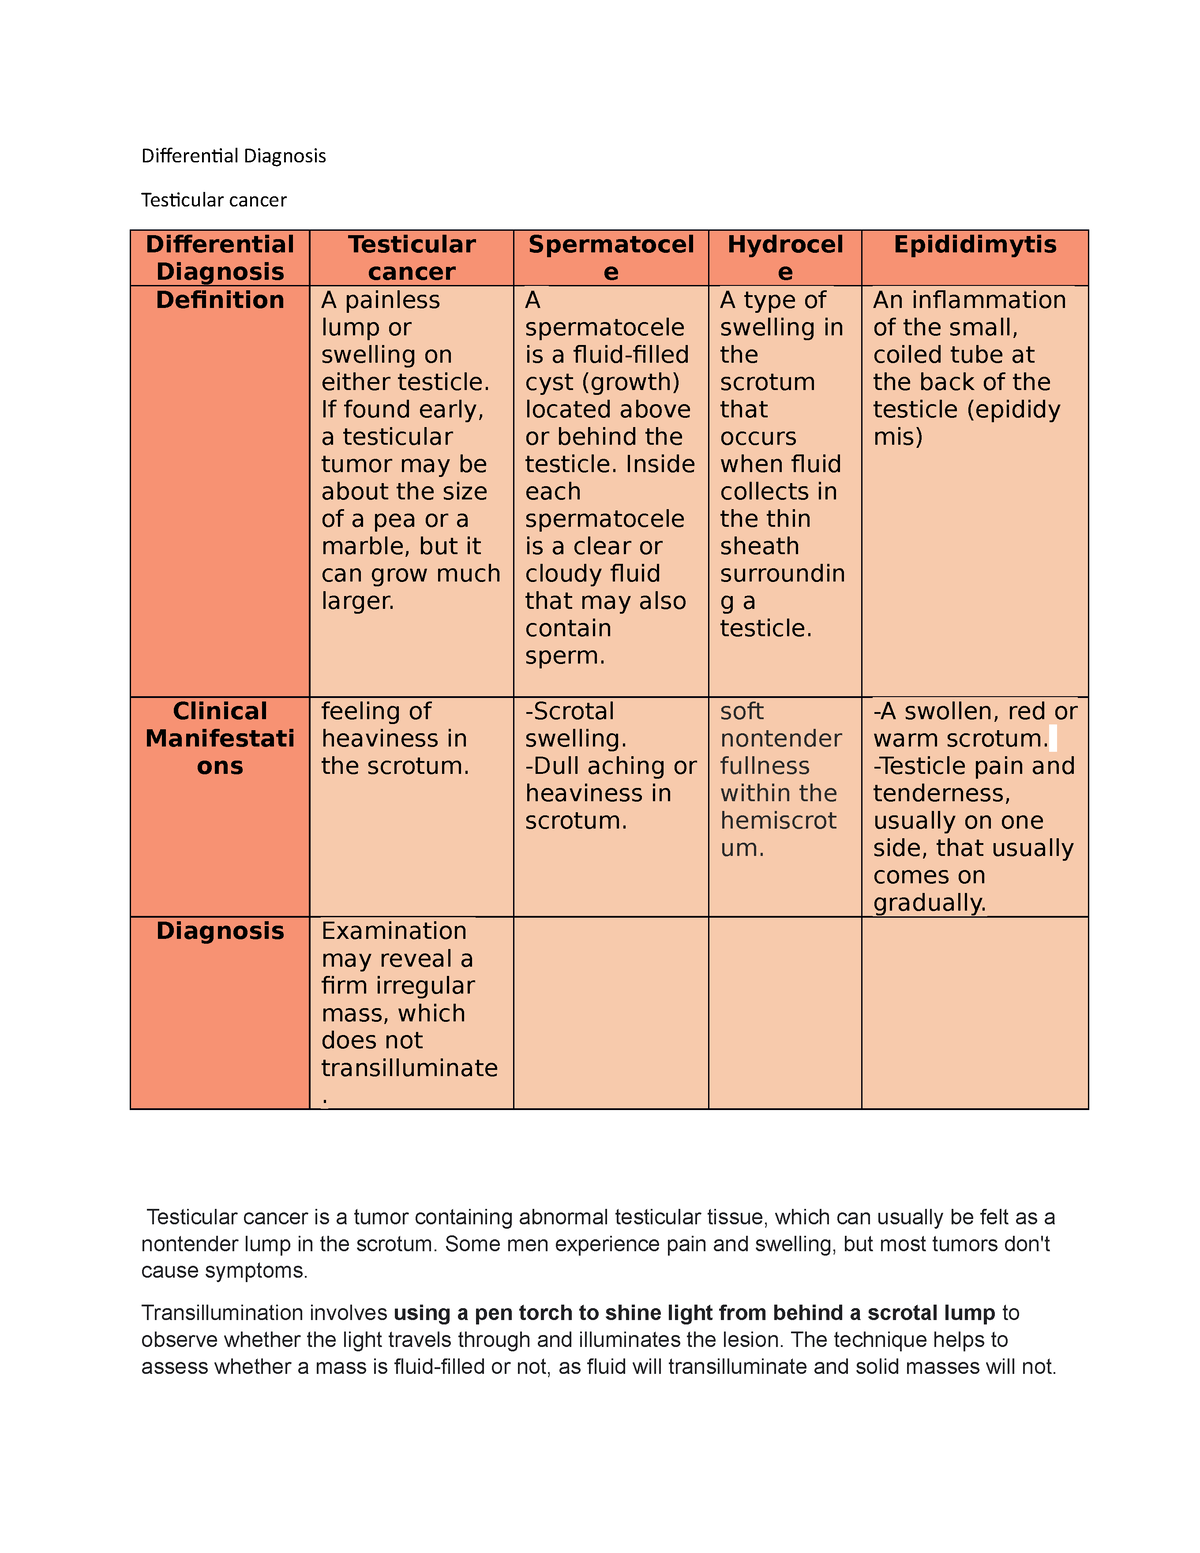

Differential Diagnosis Differential Diagnosis Testicular cancer